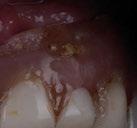

Exploración Intraoral

Presenta un estado oral deficitario. Parcialmente edéntula, con colapso de mordida, migración dental patológica, restauraciones de resina antiguas fisuradas y filtradas, transparencia y exposición de cámara pulpar secundaria a desgastes con pérdida de estructura e integridad de tejido dental importante (Figuras 1 a 4). Portadora a tiempo parcial de prótesis removibles desadaptadas de más de 10 años de antigüedad, refiriendo incapacidad de adaptación a este tipo de prótesis.

Figura 3. Visión intraoral oclusal mandibular. Figura 4. Visión intraoral frontal. Figura 1. Visión intraoral oclusal maxilar. Figura 2. Visión lateral izquierda intraoral. Figura 7. Escaneado intraoral maxilar con Dexis IS3700. Figura 8. Escaneado intraoral mandibular con Dexis IS3700. Figura 5. Visión extraoral lateral sonrisa.